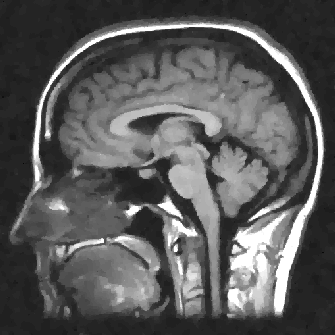

We display the noisy image and the reconstructed images from these three denoising methods in Fig. 8 111 Image retrieved from http://radiopaedia.org/ by Frank Gaillard.. To better understand the performance, we zoom in the selected part of the image and display them in Fig. 9.

We observe that the anisotropic TV suffers from the staircase artifact due to the fact that the TV is local operator. On the other hand, the reconstruction with TFV regularity has blurry effect on the edges. This is not surprising because the TFV is a non-local method and it is less edge sensitive than TV. Instead, the TV-TFV regularity avoids such artifacts and has a better reconstruction of both the edges and the overall image.

We also present the numerical results of different performance measurements in Table 3. The TV-TFV regularity shows better results in such measurements as well.